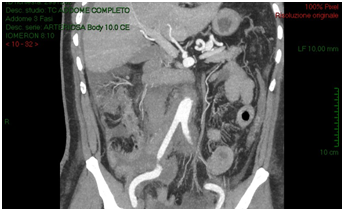

The CT-scan, targeted to a suspect of hemorrhage, did not have delayed phases. Patient received paracentesis with around 3200 cc fluid drained that was sent to microbiological examination. Result of bacteriological exam revealed infection by Proteus Mirabilis and he received target antibiotic therapy with resolution of septic status. In XXII post-operative day, for a progressive increase of serum creatinine we decided to perform an Uro-CT scan. The exam showed reduction of intraperitoneal fluid, right iliac side fluid collection with contrast enhancement during delayed phases; right ureter was not visible under fluid collection (Figure 3). We attempted to insert a ureteral stent in retrograde way but ureter resulted totally interrupted inside the fluid collection so the patient was undergone to explorative laparotomy and toilette of fluid collections. We found ureteral loss of substance of around 3 centimeter localized in anterior ureteral wall. We manufactured end-to-end ureteral anastomosis after positioning of ureteral stent seven French. We removed ureteral stent after 3 months and currently the patient is in follow-up with a good renal function as shown at last CT-scan after 10 months (Figure 4).

Figure 2: CT-scan shows increasing of intra-retroperitoneal fluid with small bowel and right colon compression and increase of right iliac region serous-hematic fluid.